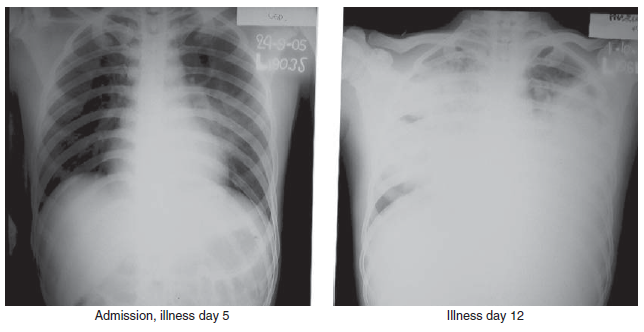

Meskipun hampir seluruh kasus H5N1 dibawa ke rumah sakit karena gejala demam, pneumonia dan hipoksia, presentasi gejala yang tidak biasa juga telah dilaporkan, seperti demam dengan diare, nausea, dan muntah [5], dan demam dengan diare, dan kejang-kejang yang melanjut menjadi koma dengan diagnosa klinis ensefalitis [59]. Durasi median dari onset penyakit sampai masuk ke rumah sakit pada 194 kasus H5N1 adalah 4 hari (kisaran 0 – 18 hari) [237]. Temuan laborairuym yang umum saat pasien pertama masuk rumah sakit meliputi leukopenia, limfopenia, trombositopenia ringan sampai moderat, dan meningkatnya transaminase [12, 201, 244]. Temuan radiografi bagian dada pada pasien H5N1 meliputi infiltrasi difus, multifokal, atau berbentuk pulau-pulau (patchy), inflintrasi interstitial, dan konsolidasi multisegmen dan lobular (Gambar 5.3 dan 5.4). Progresi sampai menjadi pneumonia bilateral dan kegagalan pernafasan yang memerlukan pemasangan mekanisme ventilasi invasif umum ditemukan. Komplikasi pada pasien H5N1 meliputi, ARDS, disfungsi multiorgan dengan penyakit ginjal dan jantung, dan koagulasi intravaskular terdissmeniasi (disseminated intravascular coagulation/DIC) dan sindroma shock mirip sepsis. DIC dan kegagalan multi organ telah dilaporkan pada kasus H5N1 pada wanita dengan kehamilan 4 bulan di China [183].

Gambar 5.3 Temuan radiografi bagian dada dari kasus infeksi virus HPAI H5N1 clade 2.1 pada pria berumur 21 tahun yang sembuh. Inflitrasi terlihat pada bidang tengah paru-paru kiri saat pemeriksaan hari ke-5. Satu minggu kemudian, infiltrat terkonsolidasi dan diffu terlihat pada seluruh bidang paru-paru. Pasien ini mengalami kesembuhan tanpa penggunakan ventilasi mekanik. Sumber: T. Uyeki, Centers for Disease Control and Prevention (CDC).